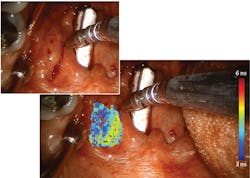

In 2010, Intuitive Surgical (Sunnyvale, CA) introduced FGS as an add-on for its da Vinci Surgical System via a module called FireFly, which uses FDA-approved indocyanine green (ICG) to provide near-infrared fluorescence (NIRF) imaging of blood flow and tissue perfusion (see Fig. 1). Released in 2000, da Vinci is used for more procedures than any other robotic surgery setup. The module is an important addition because robotic surgery removes the possibility of tactile feedback, leaving visualization as the only means of assessment. But because ICG is not a molecularly targeted probe, it lacks specificity for critical cancer assessment and cannot provide quantitative assessment of tumor margins. And the fact that ICG-based imaging requires that lights in an operating room be turned off means it does not integrate seamlessly into workflow.Searching for a more robust means of image guidance, Intuitive Surgical turned to time-resolved autofluorescence. As a label-free technique, time-resolved fluorescence spectroscopy (TRFS) relies on endogenous fluorophores as opposed to injected biomarkers, and they overcome limitations of steady-state fluorescence techniques studied for diagnosing oral cancer. The time-resolved contrast mechanism enables discrimination among fluorophores that have overlapping spectra, and it provides information about the molecular composition of tissue by revealing changes to the structural and metabolic characteristics resulting from cancer. Specifically, the approach has been demonstrated to distinguish tumors from normal tissues in head and neck cancer.

All components involved in performing ms-TRFS measurements are housed in a compact cart designed to integrate well with operating room procedures. A micro Q-switched laser, frequency-tripled to 355 nm with a 2 kHz repetition rate, supplies fluorescence excitation. The optical probe collects the fluorescence signal using a wavelength selection module (WSM) incorporating dichroic and bandpass filters that simultaneously resolve fluorescence emission into four spectral channels: 390/40 nm, 466/40 nm, 542/50 nm, and 629/53 nm. A 445 nm continuous-wave solid-state laser coupled into the 466/40 nm channel injects a 3 mW aiming beam onto the same path as the excitation beam. Optical fibers of differing lengths (to act as delays) couple with the four channels into a single detector (a microchannel plate photomultiplier tube). The PMT detects the fluorescence signals and converts them to electrical signal, which an RF amplifier processes before sending to a high-speed digitizer for sampling at 80 ps time intervals. The system modulates the photodetector’s bias voltage (and gain) in real time to handle signal changes resulting from differing signal-generation abilities of particular tissue types, as well as differences in probe-to-tissue distance. An AC-coupled amplifier filters out autofluorescence induced by the aiming beam.A computer receives freehand scanning data from the optical fiber-probe along with white-light video from a frame grabber that processes the endoscopy input. It correlates the locations of these inputs and sends them to the display with ms-TRFS data—depicting biochemical properties of tissue as fluorescence parameters—overlaid onto the video stream (see image above).